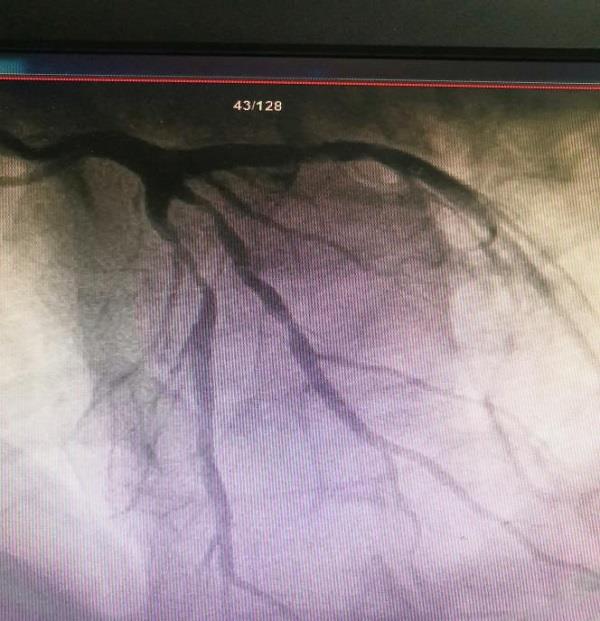

科室治疗组详细询问胡先生病情并组织讨论,制定治疗方案、完善术前检查后,心血管内科介入手术团队对胡先生行冠脉造影检查,结果证实冠状动脉前降支钙化伴重度狭窄(85%以上狭窄),并影响远端血流流速,粗大对角支近段狭窄80%。在胡先生和家属同意下,介入手术团队在前降支成功植入1枚支架后,血管狭窄消失,对角支狭窄处给予冠状动脉药物球囊治疗,血管狭窄明显减轻,病变血流恢复正常,胡先生胸痛胸闷症状得以缓解。手术后,胡先生身体健康状况恢复良好,家人感激不已,随送来一面锦旗以表谢意。

治疗前,前降支和对角支重度狭窄